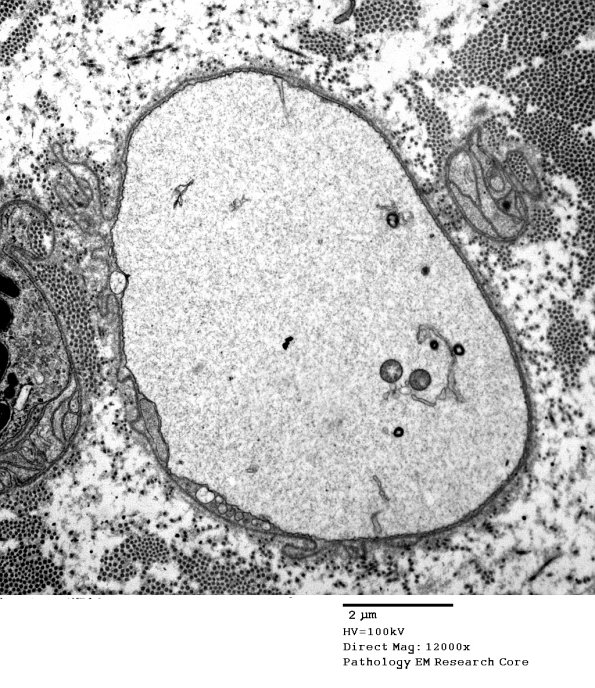

2B1,2 This structure superficially resembles a demyelinated axon although it does not have the expected axonal cytoskeleton and the company it keeps is with degenerating axons not other demyelinated/remyelinated axons. (electron micrographs)